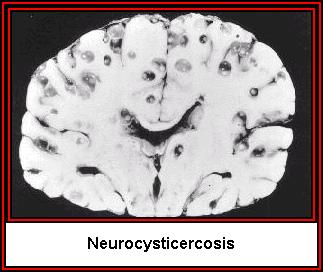

- Documenting the pathological effects of parasitism

We will cover the basic biology, pathology, and epidemiology of important human parasites. The course is divided into two parts: protozoan and worm parasites. In both sections we will discuss the basics of host/parasite interactions, as well as the medical affects of parasitism on humans.